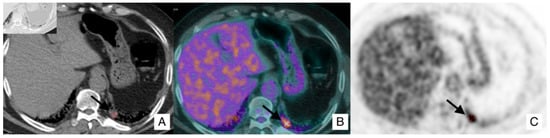

4.1. Lung Cancer

- In case of an IPF patient having a nodule of <8 mm, an HRCT is needed every three–six months with continuous surveillance. If the HRCT demonstrates progression of the nodule, a PET-CT is recommended;

- In case of an IPF patient having a nodule of at least 8 mm, a PET-CT scan is highly recommended. If the PET reports a great uptake, the panel expert state that “minimally invasive procedures are needed, such as TTNB (Transthoracic needle biopsy) or a CT-TTNB for peripheral lesions or endobronchial ultrasound-guided transbronchial needle biopsy (EBUS-guided transbronchial needle biopsy) if there are pathological lymph nodes (≥8 mm)” [35]. If biopsy could be unsafe for the patient, or not indicated for the clinical context, “it is suggested a multidisciplinary and personalized approach”;

- In case of a patient having an advanced lesion on the HRCT (mass or nodule greater than 8 mm), a multidisciplinary and personalized approach is needed; based on the clinical conditions of the patient, in these cases, the panel experts state that “no further diagnostic procedures could be adopted” [35]—planning a personalized approach, based also on palliative support.